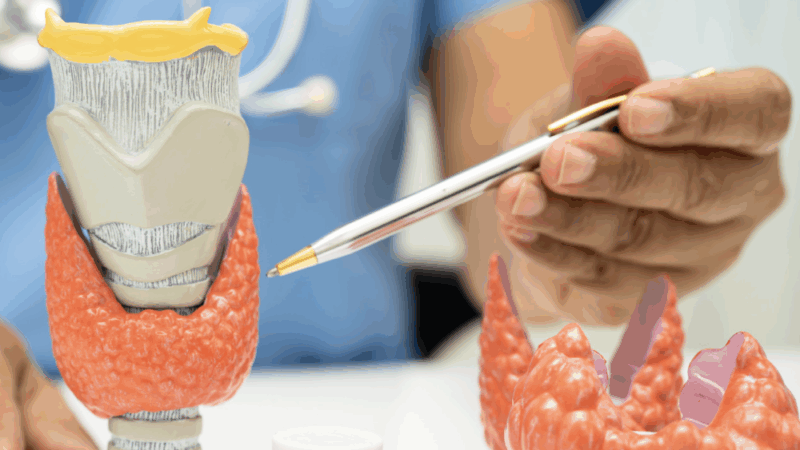

Anticuerpos Anti tiroideos

Las enfermedades tiroideas autoinmunes son actualmente ...